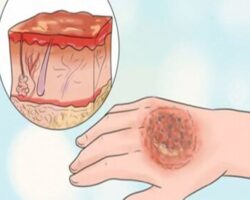

بیشتر بخوانید تعبیه فیبرهای نوری در پارچه برای درمان امراض پوستی

تعبیه فیبرهای نوری در پارچه برای درمان امراض پوستی تهران – ایرنا - محققان فرانسوی نوعی پارچه موسوم به Fluxmedicare تولید کردند که در آن فیبرهای نوری و یک سیستم ...